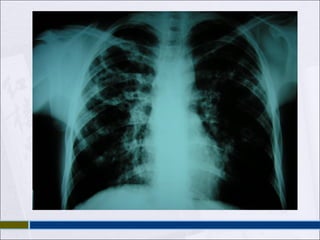

 PAR RADIOLOGICOY PROY. LORDOTICA  MÁS FRECUENTE INFILTRADO EN SEGM APICALES DE LÓB SUP Y EN SEGM SUPERIORES DE LÓBULOS INF.  PUEDE APARECER CAVITACIÓN.

• #37 Radiografía de tórax En la primoinfección tuberculosa, es típica la aparición de un infiltrado en las regiones medias del pulmón, por ser éstas las mejor ventiladas. Es posible ver un ensanchamiento hiliar y mediastínico por agrandamiento de los ganglios. Las lesiones primarias curadas pueden dejar un nódulo periférico calcificado, que, junto con un ganglio hiliar calcificado es lo que se conoce clásicamente como Complejo de Ghon. En la tuberculosis de reactivación, la imagen radiológica más frecuente es la aparición de un infiltrado en los segmentos apicales de los lóbulos superiores, y en los segmentos superiores de los lóbulos inferiores. Además del infiltrado, puede aparecer cavitación. A veces, la imagen es más clara en una proyección lordótica, que facilita la visión de imágenes que pueden estar ocultas por la confluencia de las primeras costillas y la clavícula. Cuando existe diseminación broncógena, se puede observar un imagen más extensa, con patrón destructivo. En la diseminación hematógena es característica la afectación pulmonar, cuya imagen en la radiografía de tórax se denomina patrón miliar (por la similitud con las semillas de mijo). Este patrón se caracteriza por la imagen de pequeños nódulos de unos 2 mm, repartidos de forma difusa y homogénea por ambos campos pulmonares. Es mejor observada en la radiografía lateral. Términos como &amp;quot;lesiones fibróticas&amp;quot;, &amp;quot;cicatriciales&amp;quot;, &amp;quot;inactivas&amp;quot;, se deberían evitar en la evaluación de una sola radiografía de tórax, pues la inactividad de una tuberculosis pulmonar no se puede afirmar por una imagen aislada. Sin embargo, aquellas imágenes que no cambian en radiografías seriadas durante 3 ó 4 meses si son más sugestivas de una tuberculosis antigua (o de otro proceso). Es frecuente ver en estas lesiones antiguas retracciones del hilio pulmonar o desviación de la tráquea. Dicho esto, hay que saber que la tuberculosis se puede manifestar radiológicamente con cualquier tipo de imagen, incluso con radiografía normal. En un estudio publicado en la revista Chest en el año 1999, los enfermos con radiografía normal y cultivo positivo suponían el 4,8 por ciento del total de los 518 pacientes con cultivo de esputo positivo de su serie (todos tenían clínica: tos de más de un mes de evolución, fiebre de más de una semana, o habían tenido una conversión del PPD en los dos últimos años). La presentación radiológica en el VIH difiere de la del inmunocompetente, de forma que cuanto más inmunodeprimido esté el enfermo, más probable es que la imagen difiera de la típica ya comentada. Esta presentación radiológica es muy variable, desde la radiografía normal (más frecuente que en el inmunocompetente, del 5 al 10 por ciento de los casos con cultivo positivo según las series), hasta extensos infiltrados pulmonares bilaterales que confundan el cuadro con una neumonía por P. carinii. Suelen estar ausentes los signos clásicos de cavitación, que sólo aparecen en un 10 por ciento de los casos, siendo menos frecuente cuanto mayor sea el grado de inmunosupresión. Es de destacar la alta frecuencia de adenopatías intratorácicas, que se presentan en el 50 por ciento de los paciente con tuberculosis pulmonar. No es raro el derrame pleural, de presentación clínica similar a los inmunocompetentes. Como en éstos, la tuberculosis sigue siendo la principal causa de derrame pleural en los pacientes VIH positivos, aunque otras infecciones (criptococosis, neumonías bacterianas, endocarditis derecha en pacientes usuarios de drogas intravenosas) y tumores (sarcoma de Kaposi, linfoma no Hodgkin), pueden causarlo con frecuencia. Debe recordarse, además, que en nuestro medio la tuberculosis pulmonar es una de las complicaciones que con mayor frecuencia se asocia al desarrollo de neumotórax espontáneo, y que debe considerarse en le diagnóstico diferencial, junto con la neumonía por P. carinii (especialmente recibe pentamidina en aerosol como profilaxis) y las neumonías bacterianas. La afectación parenquimatosa por tuberculosis puede originar cualquier tipo de infiltrado radiológico. No existe predilección por ninguna localización ni patrón específicos, o por la extensión de la afectación. La tuberculosis no debe ser excluida ni confirmada por el aspecto del infiltrado radiológico, y en este sentido es una de las grandes simuladoras. Sólo el patrón miliar tiene una alta especificidad en el diagnóstico de tuberculosis. Un fenómeno digno de ser mencionado en los enfermos VIH-positivos con tuberculosis es el empeoramiento transitorio que se puede producir en la imagen radiológica tras el inicio del tratamiento antirretroviral. Este empeoramiento se puede manifestar como aumento de infiltrados previos, aparición de adenopatías o derrame pleural. También pueden aparecer lesiones en zonas radiológicamente normales en placas previas. Puede acompañarse de fiebre. Suele ocurrir entre 1 y 5 semanas tras el inicio del tratamiento antirretroviral. Estos episodios son similares en su presentación a las ya descritas desde hace mucho tiempo, pero mucho menos frecuentes, respuestas paradógicas que pueden aparecer tras el inicio del tratamiento tuberculostático. El fenómeno puede ser el resultado de la recuperación del sistema inmunológico, como sugiere el hecho de que se recupera la reacción de hipersensibilidad a la tuberculina en pacientes que previamente eran anérgicos. Tras excluir otras infecciones concomitantes, el tratamiento antirretroviral se debe mantener, y considerar la utilización de corticoides para el control de los síntomas.